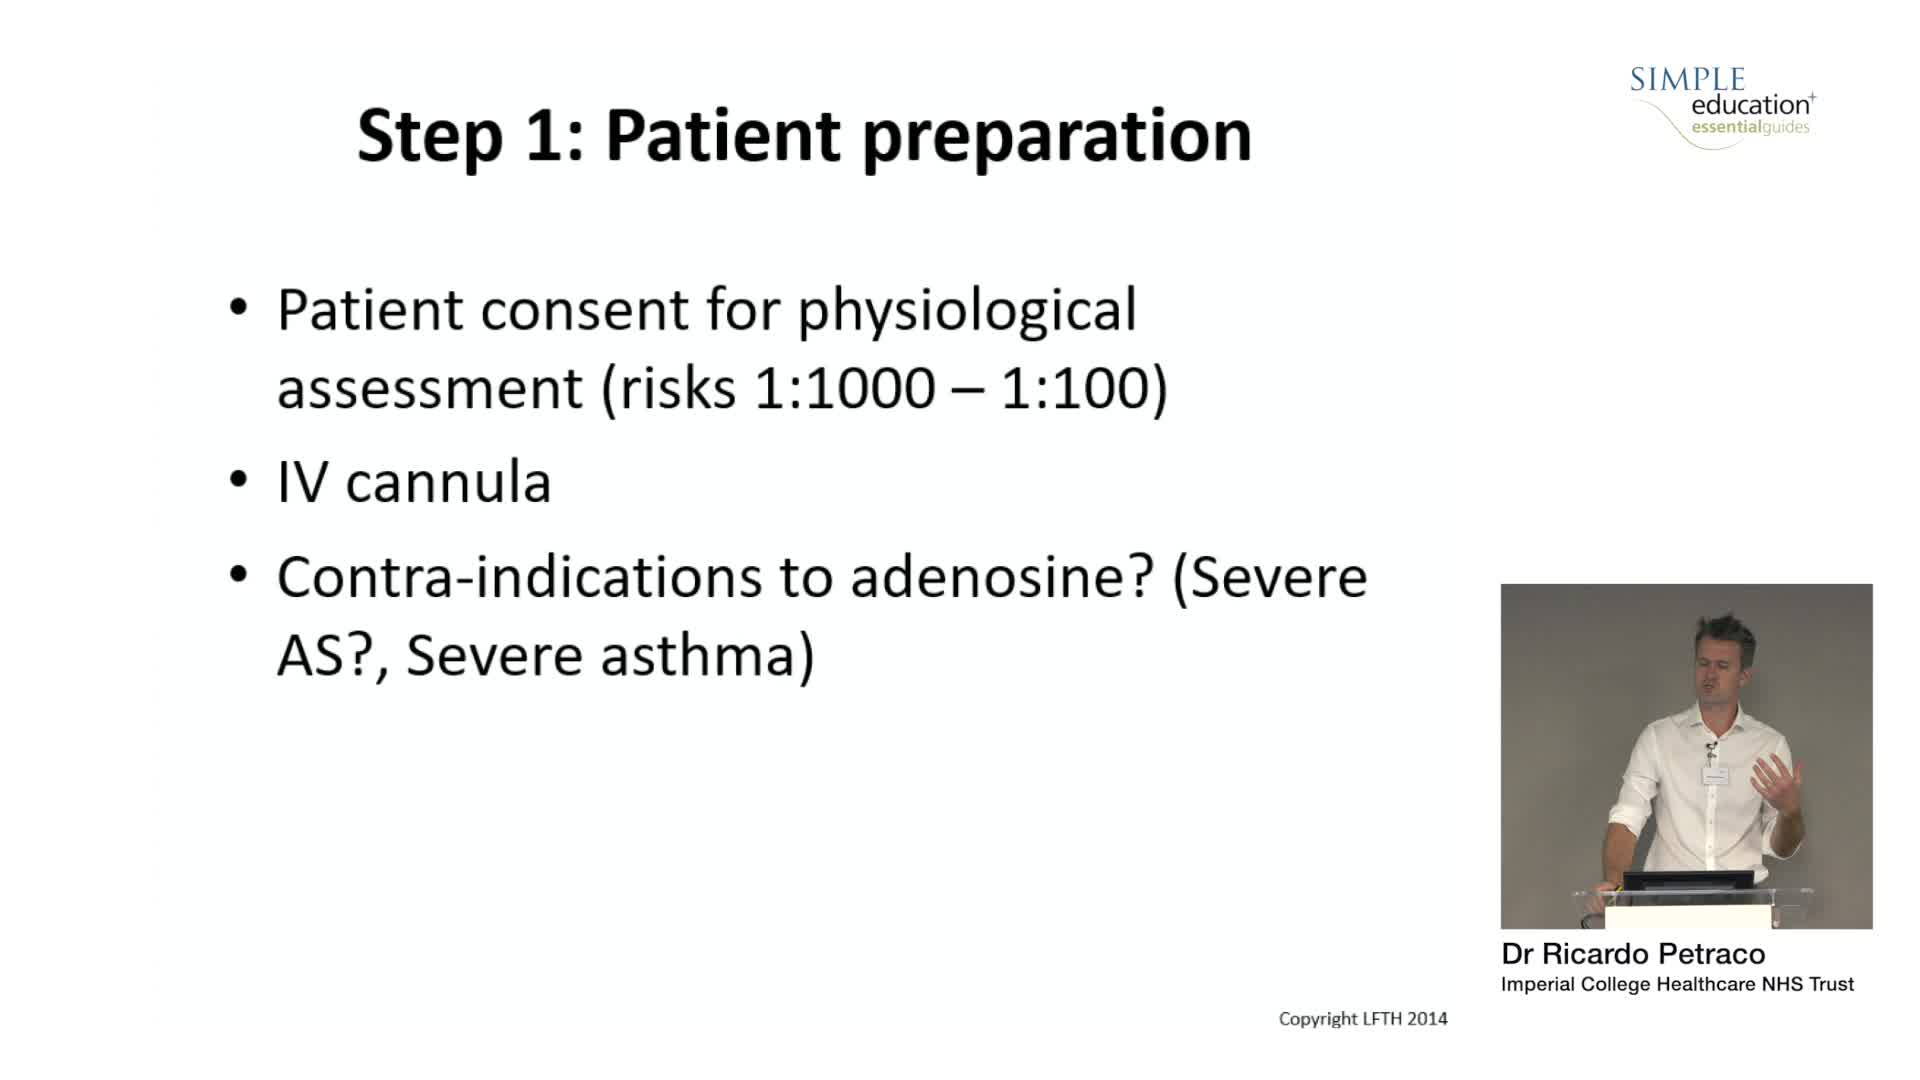

Breakout session: Common pitfalls of FFR and iFR assessment - Dr Ricardo Petraco

How to perform iFR and FFR, and best-practice measurement tips and tricks - Dr Ricardo Petraco

ABC for using Coronary Physiology in Aortic Stenosis, Primary Percutaneous Coronary Intervention (PPCI)/ACS, Muscle Bridges and Atrial Fibrillation - Dr Ricardo Petraco